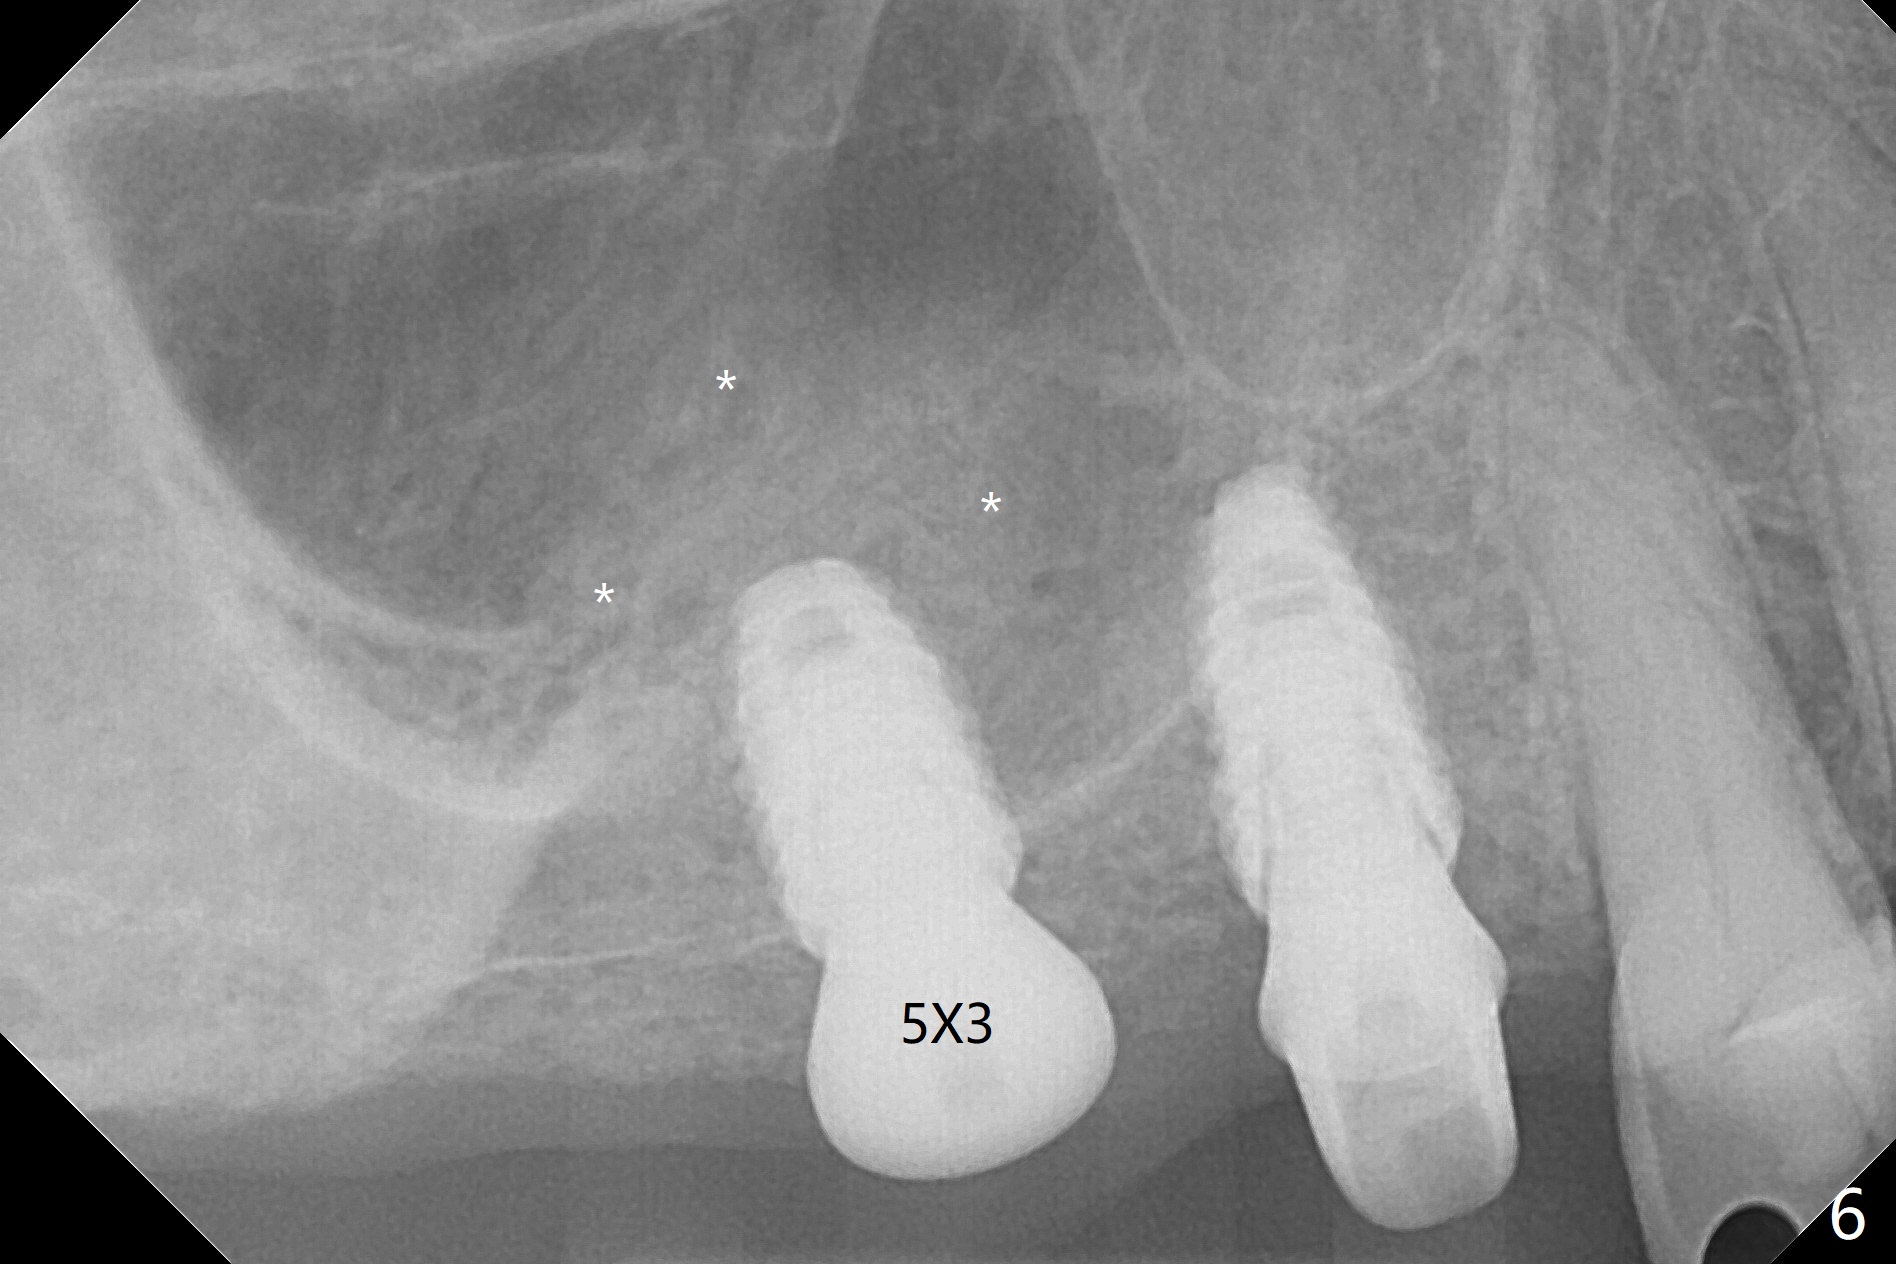

Osteotomy at #3 is performed last (Fig.1,2); as planned, a 4 mm cortical tap is used with guide for sinus lift. Unfortunately the sinus membrane is perforated. Implant placement is aborted. Instead Osteogen plug is inserted into the osteotomy, which is fixed in place by acrylic extending from the provisional at #4. Osteotomy for #3 implant will be attempted with control of the depth in 4 months. The patient has allergy to Amoxicillin (rash). When switching to Clindamycin, she develops diarrhea and loses 10 pounds. There is no abnormality at the site of #3 or 4 nearly 3 months postop (Fig.3). The next surgery will be most likely conducted without antibiotic 4 months postop. Try to draw blood for PRF. Take PA for #12 and 13 for possible impression. Remove the 3 temporary crowns, seat the guide across the arch and use no-stop fixture mounts at #4, and possibly 12 and 13. Follow the original drill sequence (check perforation after each drill, Fig.11) and use DIONavi sinus approach kit. Also load an appropriate stop for the round bur for sinus lift before hand. Mixture allograft with Metronidazole and PRF. In fact everything goes on as smoothly as planned. Osteotomy at #3 is underprep (3.5 mm in diameter drill instead of 4.0). The sinus floor appears to remain to be absent; 3.2 mm round bur is used for lift, alternating with water pumping. Following insertion of 3 pieces of PRF membranes and Vanilla Graft (Fig.4 *), a 4x10 mm dummy implant is placed. After additional bone graft (Fig.5 *), a final 4.5x7.3 mm implant is placed ~10 Ncm. The implant is placed deeper ~ 1 mm, followed by a 5.5x3 mm healing abutment (Fig.6). The implants at #12 and 13 seem to have osteointegrated (Fig.7). Impression is taken for #4, 12 and 13 with limited vertical space (Fig.8,9). An implant at #14 is being considered. There is faint bone graft around the apex of the implant 4 months postop (Fig.10). The implant sustains 25-30 Ncm torque when a 5.2x4(3) mm cemented abutment is placed. A permanent crown is cemented nearly 5 months postop (Fig.11). For the best cosmetic and masticating results, the occlusal surface should have certain degree of morphology, such as the buccal cusps (Fig.12 white curved lines). The abutment at #3 is placed and torqued to 30 Ncm before re-cementation of the repaired crown (increased occlusal surface contact). In fact the abutment at #4 is incompletely seated with a gap (Fig.13 <). The composite at #5 is dislodged while #3 crown is being repaired (*). The abutment at #4 is loose >1 year post cementation. The abutment remains incompletely seated (gap and longer apical space (double arrows)) when the abutment/crown complex rotates lingual mesiobuccal (Fig.14 curved arrow). Further proximal reduction and lingual rotation distobuccal leads to complete seating (Fig.15). It appears that incomplete seating at #13 is associated with hex mismatch (Fig.16, large apical space), which will be fixed next visit. One week later, the crown and abutment of #4 are seated together after crown repair (Fig.17). Since the abutment margin is subgingival, the crown is cemented, removed with abutment for residual cement removal and reseated with the abutment with torque at 30 Ncm. After this, the crown and abutment of #13 is reseated after mesiobuccal surface is trimmed (Fig.18), followed by pick up impression. A few days later, the crown/abutment are inserted together smoothly, the former cemented and the complex unscrewed for residual cement removal and last torqued at 30 Ncm without any X-ray confirmation.